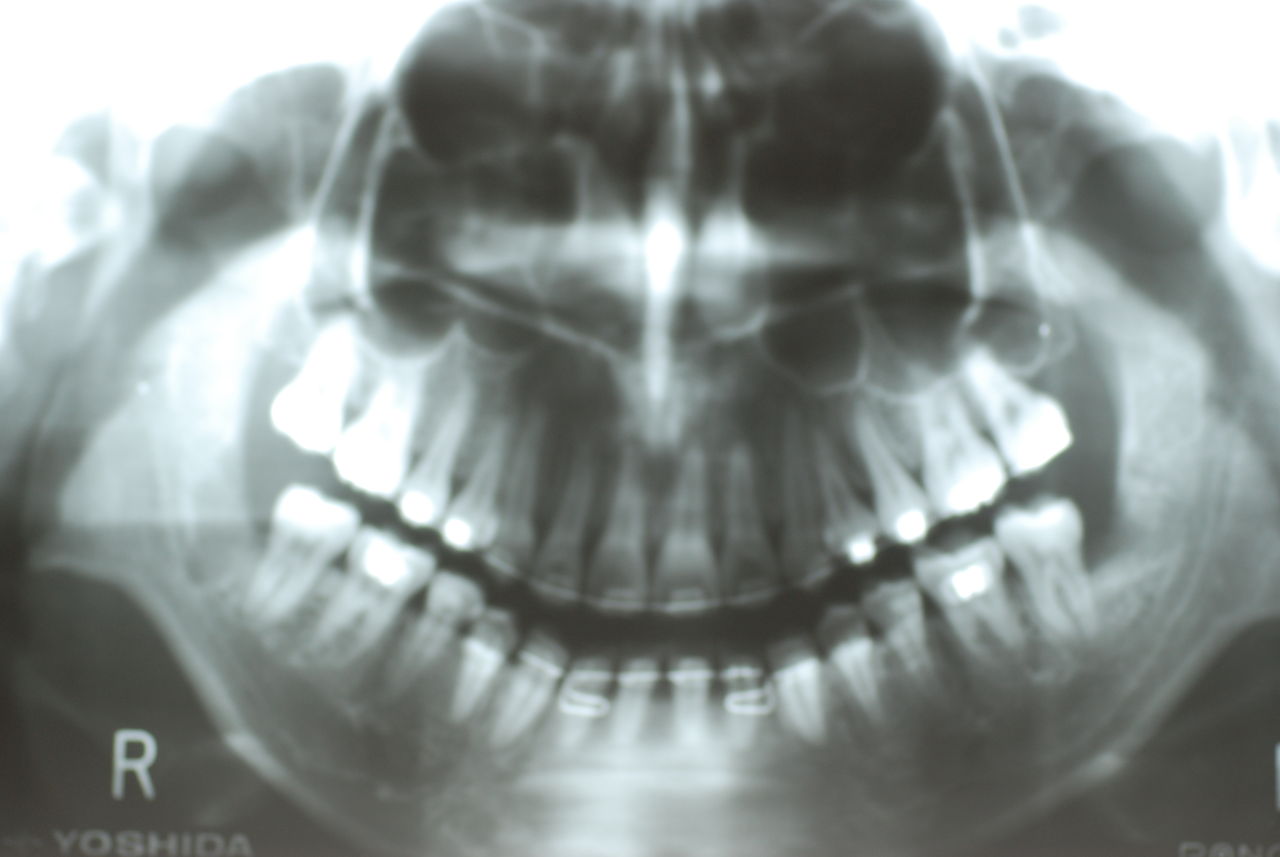

他の都心の矯正歯科で治療中で、ほぼ終了近くの方でした。歯並びで言えば上下の歯が突出していて唇が閉じにくいというのをなんとかしたい。そして歯を抜かないで出来るところを探して都心の矯正歯科への通院となりました。ところが本人曰くよく噛めないというのです。

相談しても“問題無い”の説明だけだそうです。調べたところ歯周病は進行しているし、奥歯の大きい歯2本ずつ計4本はしっかり噛んでいないのです。よく噛めないというのはそのことのようでした。これを矯正的に元に戻すことはできない訳ではありませんが、時間と手間がかかるのは間違いないことです。